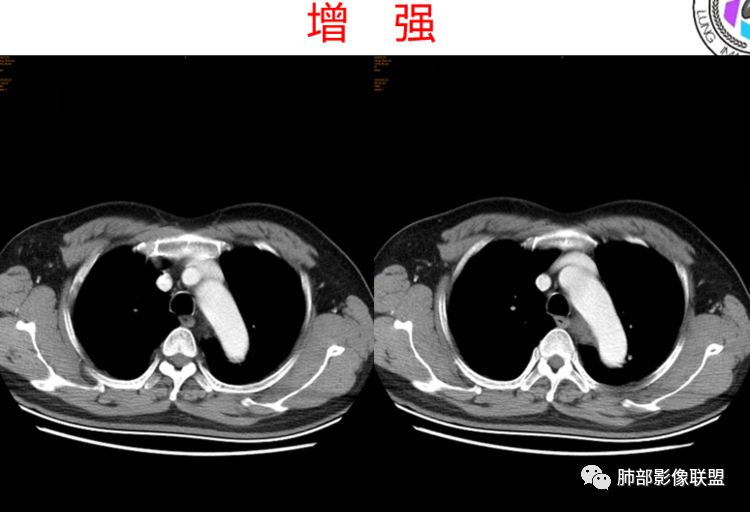

患者,男,43岁,无意间发现纵隔肿物,无胸闷胸痛,无心慌气短,无咳嗽,无吞咽困难等不适。体检发现的,无症状。

气管、左主支气管后方,食道左侧囊性占位,壁薄且均匀、光滑。气管及左主支气管受压凹陷、变形。

食道也受压变形、移位。